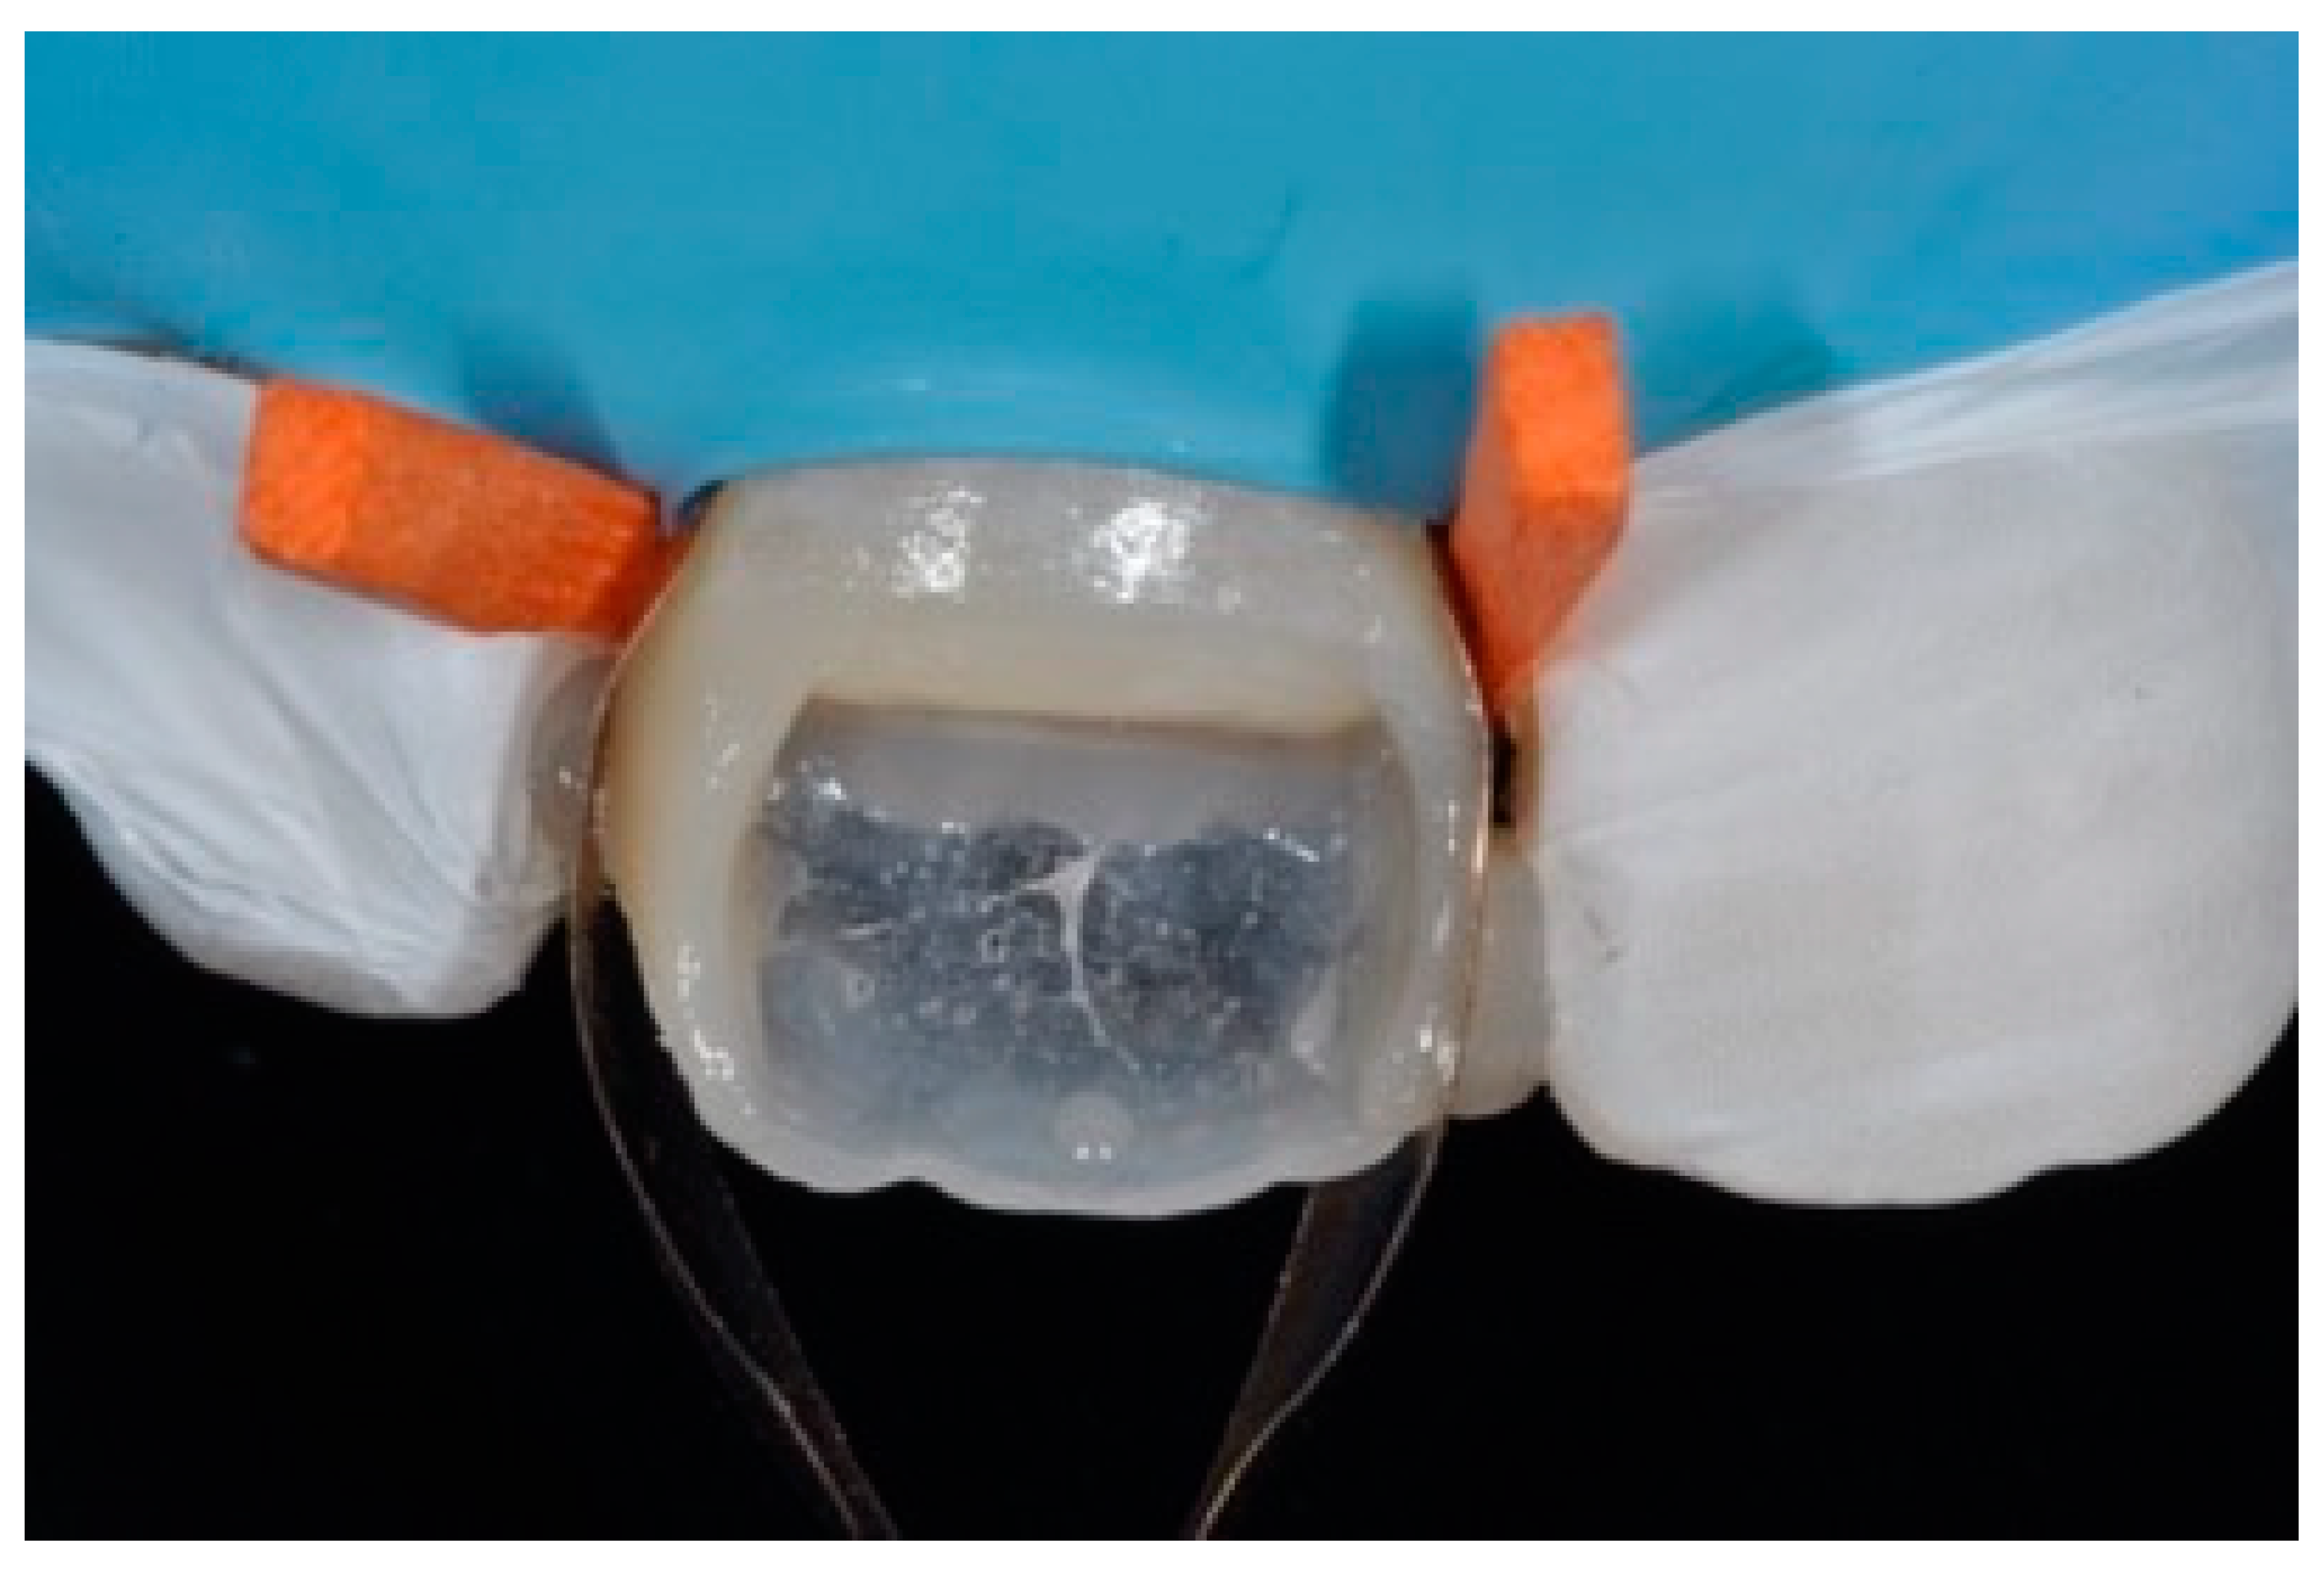

The internal ones can be reduced with diamond burs (WL 268 014 Horico, Berlin, Germany) (Figure 8).

Figure 8.

Excessive thickness of interproximal walls is reduced with a low-speed diamond bur. Reprinted from Restauri diretti nei settori anteriori, G. Paolone, S. Scolavino, © 2021, with permission from Quintessence Publishing Italy.